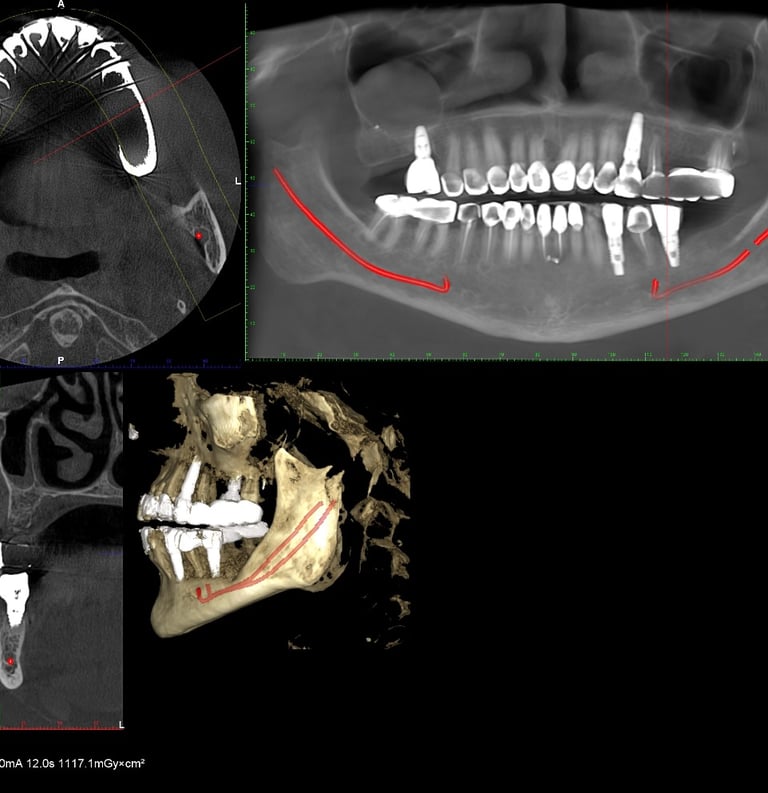

Dr. Z.R. Khan is an accomplished Oral Surgeon, proficient in a wide range of procedures from routine extractions and restorative and periodontal procedures to complex pre-prosthetic surgeries like ridge augmentation and sinus lifts for implant placement.